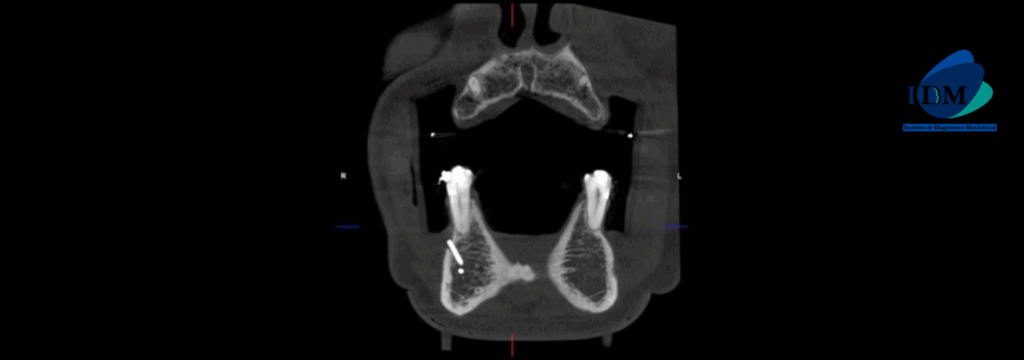

A la evaluación de la tomografía computarizada en vistas axiales, sagitales y coronal se puede observar la ausencia del agujero mentoniano del lado izquierdo y la continuidad de la tabla ósea vestibular en zona de premolares, sin embardo si se observan conductos incisivos vestibulares.

CORTES CORONALES